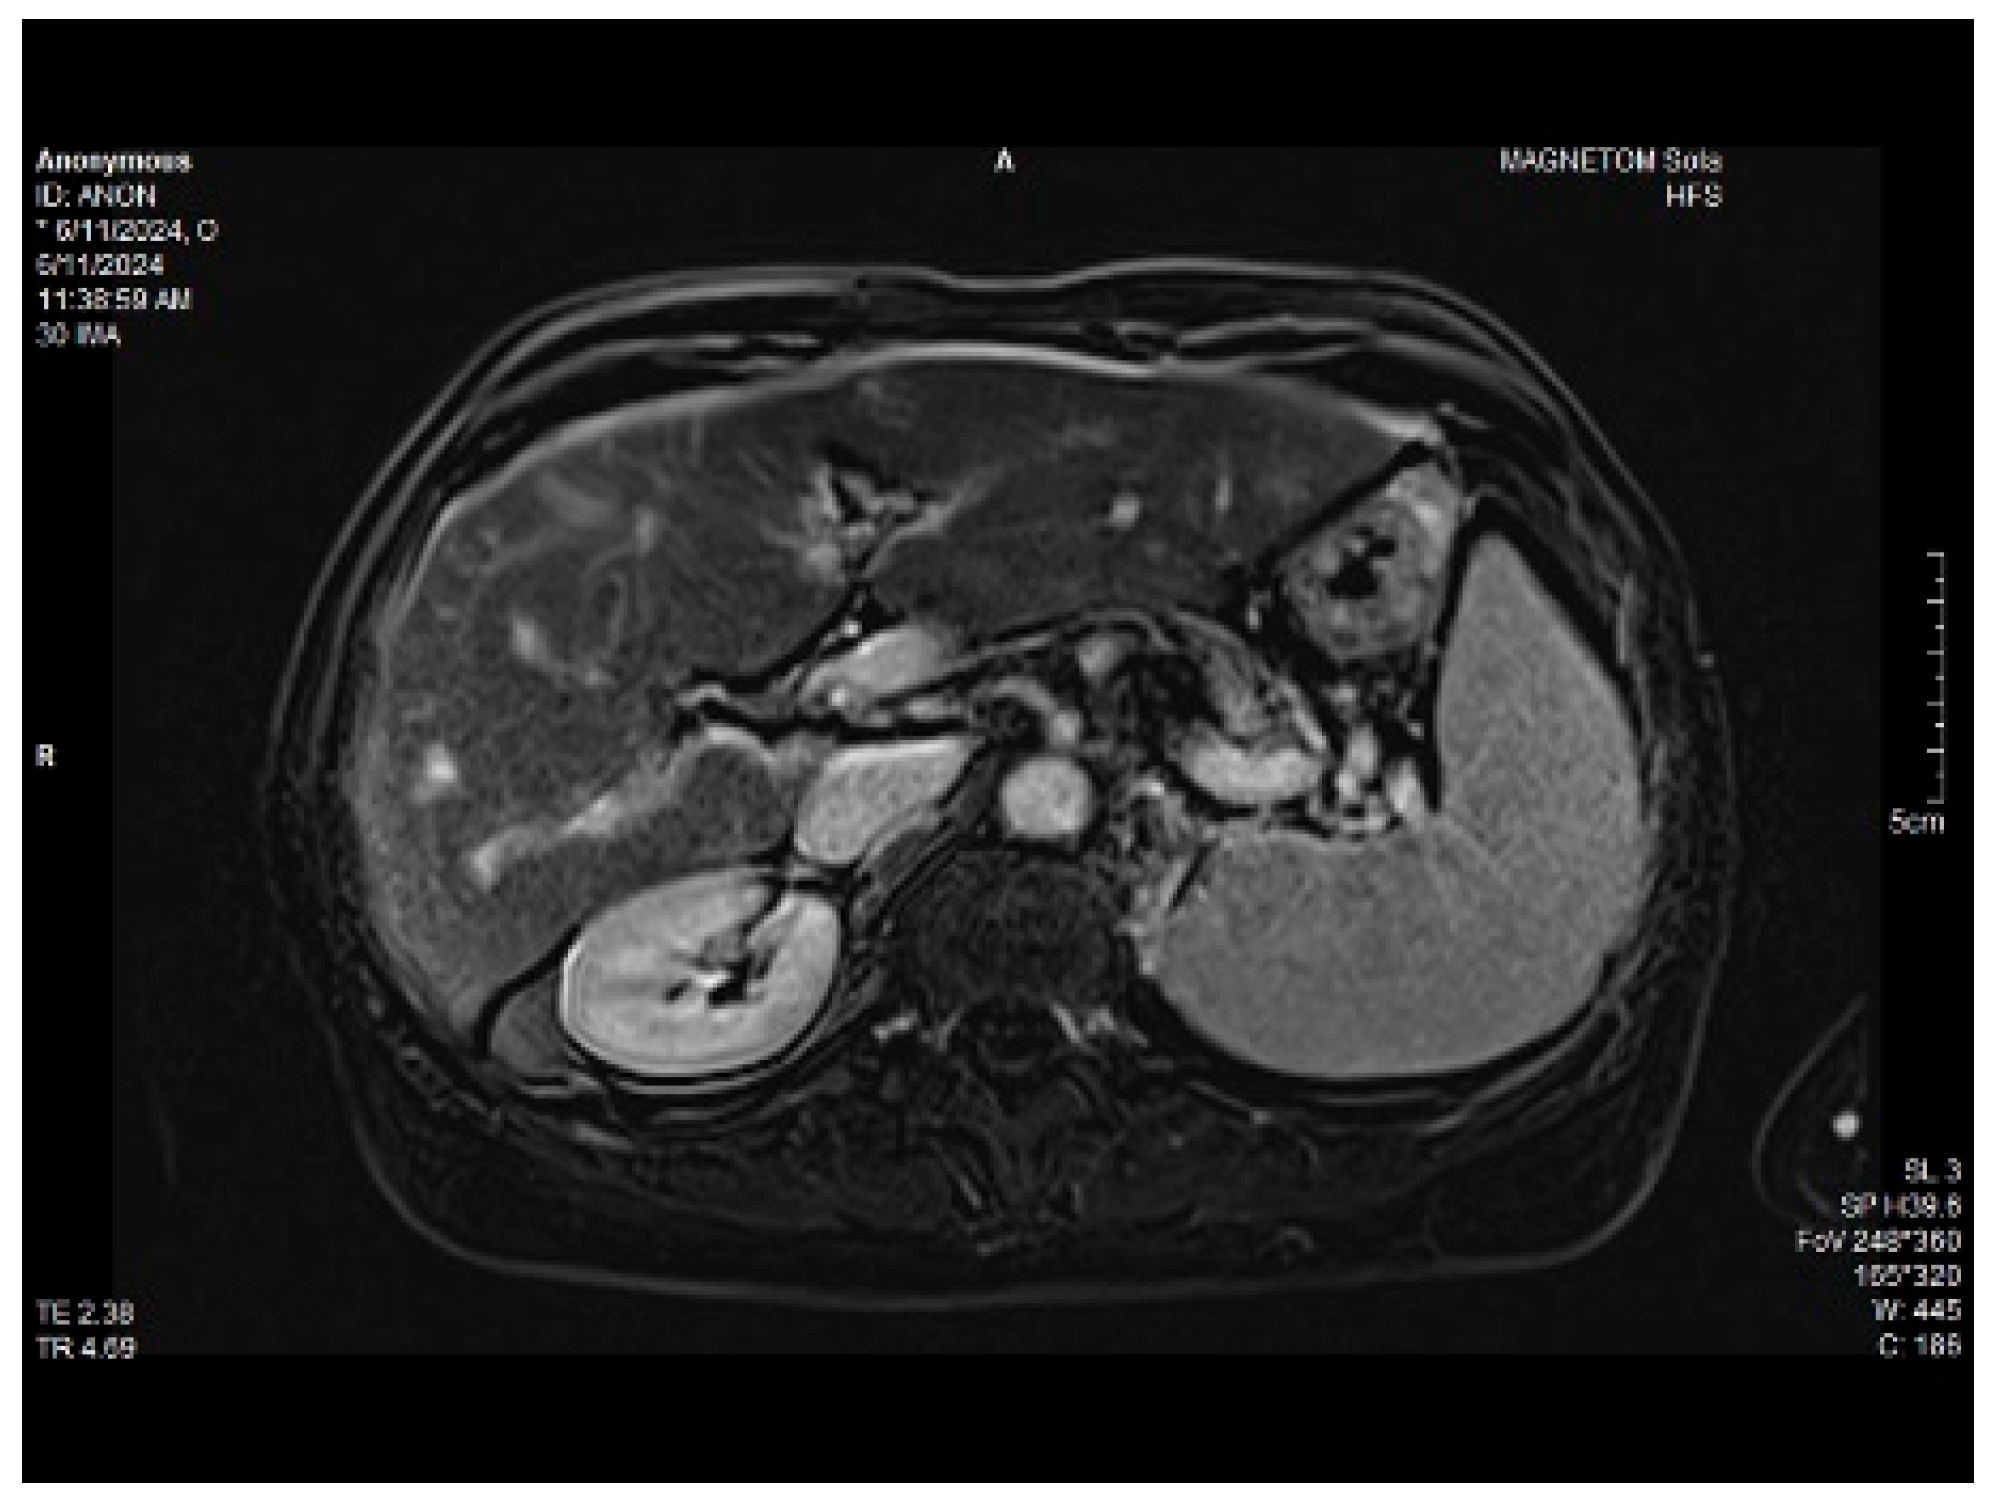

Abdominal MRI study confirmed the hepato-splenomegaly, ascites and the patency of the portal vein system. In addition, small veno-portal shunts were highlighted at the periphery of both hepatic lobes. Various MRI features are depicted in Figure 6, Figure 7, Figure 8 and Figure 9.

Figure 6. MRI featuring perihepatic and perisplenic ascites.

Figure 8. Massive thickening of the gallbladder wall, MRI features.